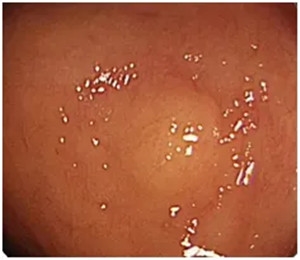

它在内镜下长这个样子

小小的,看起来很是人畜无害

或者这个样子

很容易被漏诊!